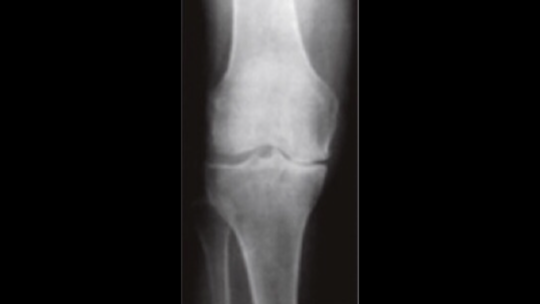

Reeducationが行う膝関節へのアプローチ

膝関節痛が起こるメカイズム

膝痛を発症する方の多くは、「体幹部分の問題!」も視野に入れなければなりません。

なぜかというと、膝が悪くなる理由の1つに「歩行時に体幹がブレることにより膝が内側に入る!」ことが

大きな問題点となります。

その歩行時には、体幹部分と膝関節は連動して動くからです。

要するに、膝痛のリハビリのキーポイントは、「膝の機能を修正すること!」「歩行時に膝が内側に入らないような動作修正!」

ここが大きなキーポイントになります。

膝痛になり膝が内側に入ると靭帯や半月板が痛みます

がまっすぐ落ちれば、膝の中にある半月板にかかる負荷が内側50% 外側50%ずつの圧力がかかります。

しかし、膝が内側に入ることで半月板にかかる負荷が変わります。

例えば、内側70% 外側30%と負荷が変わることにより内側へのストレスが高くなることによって痛みが出やすい環境になります。

だから、膝関節の機能を修正させながら、「動作も修正!」していくことがキーポイントになります。

上記の写真をみてわかるように膝が内側に入っているのがわかります。